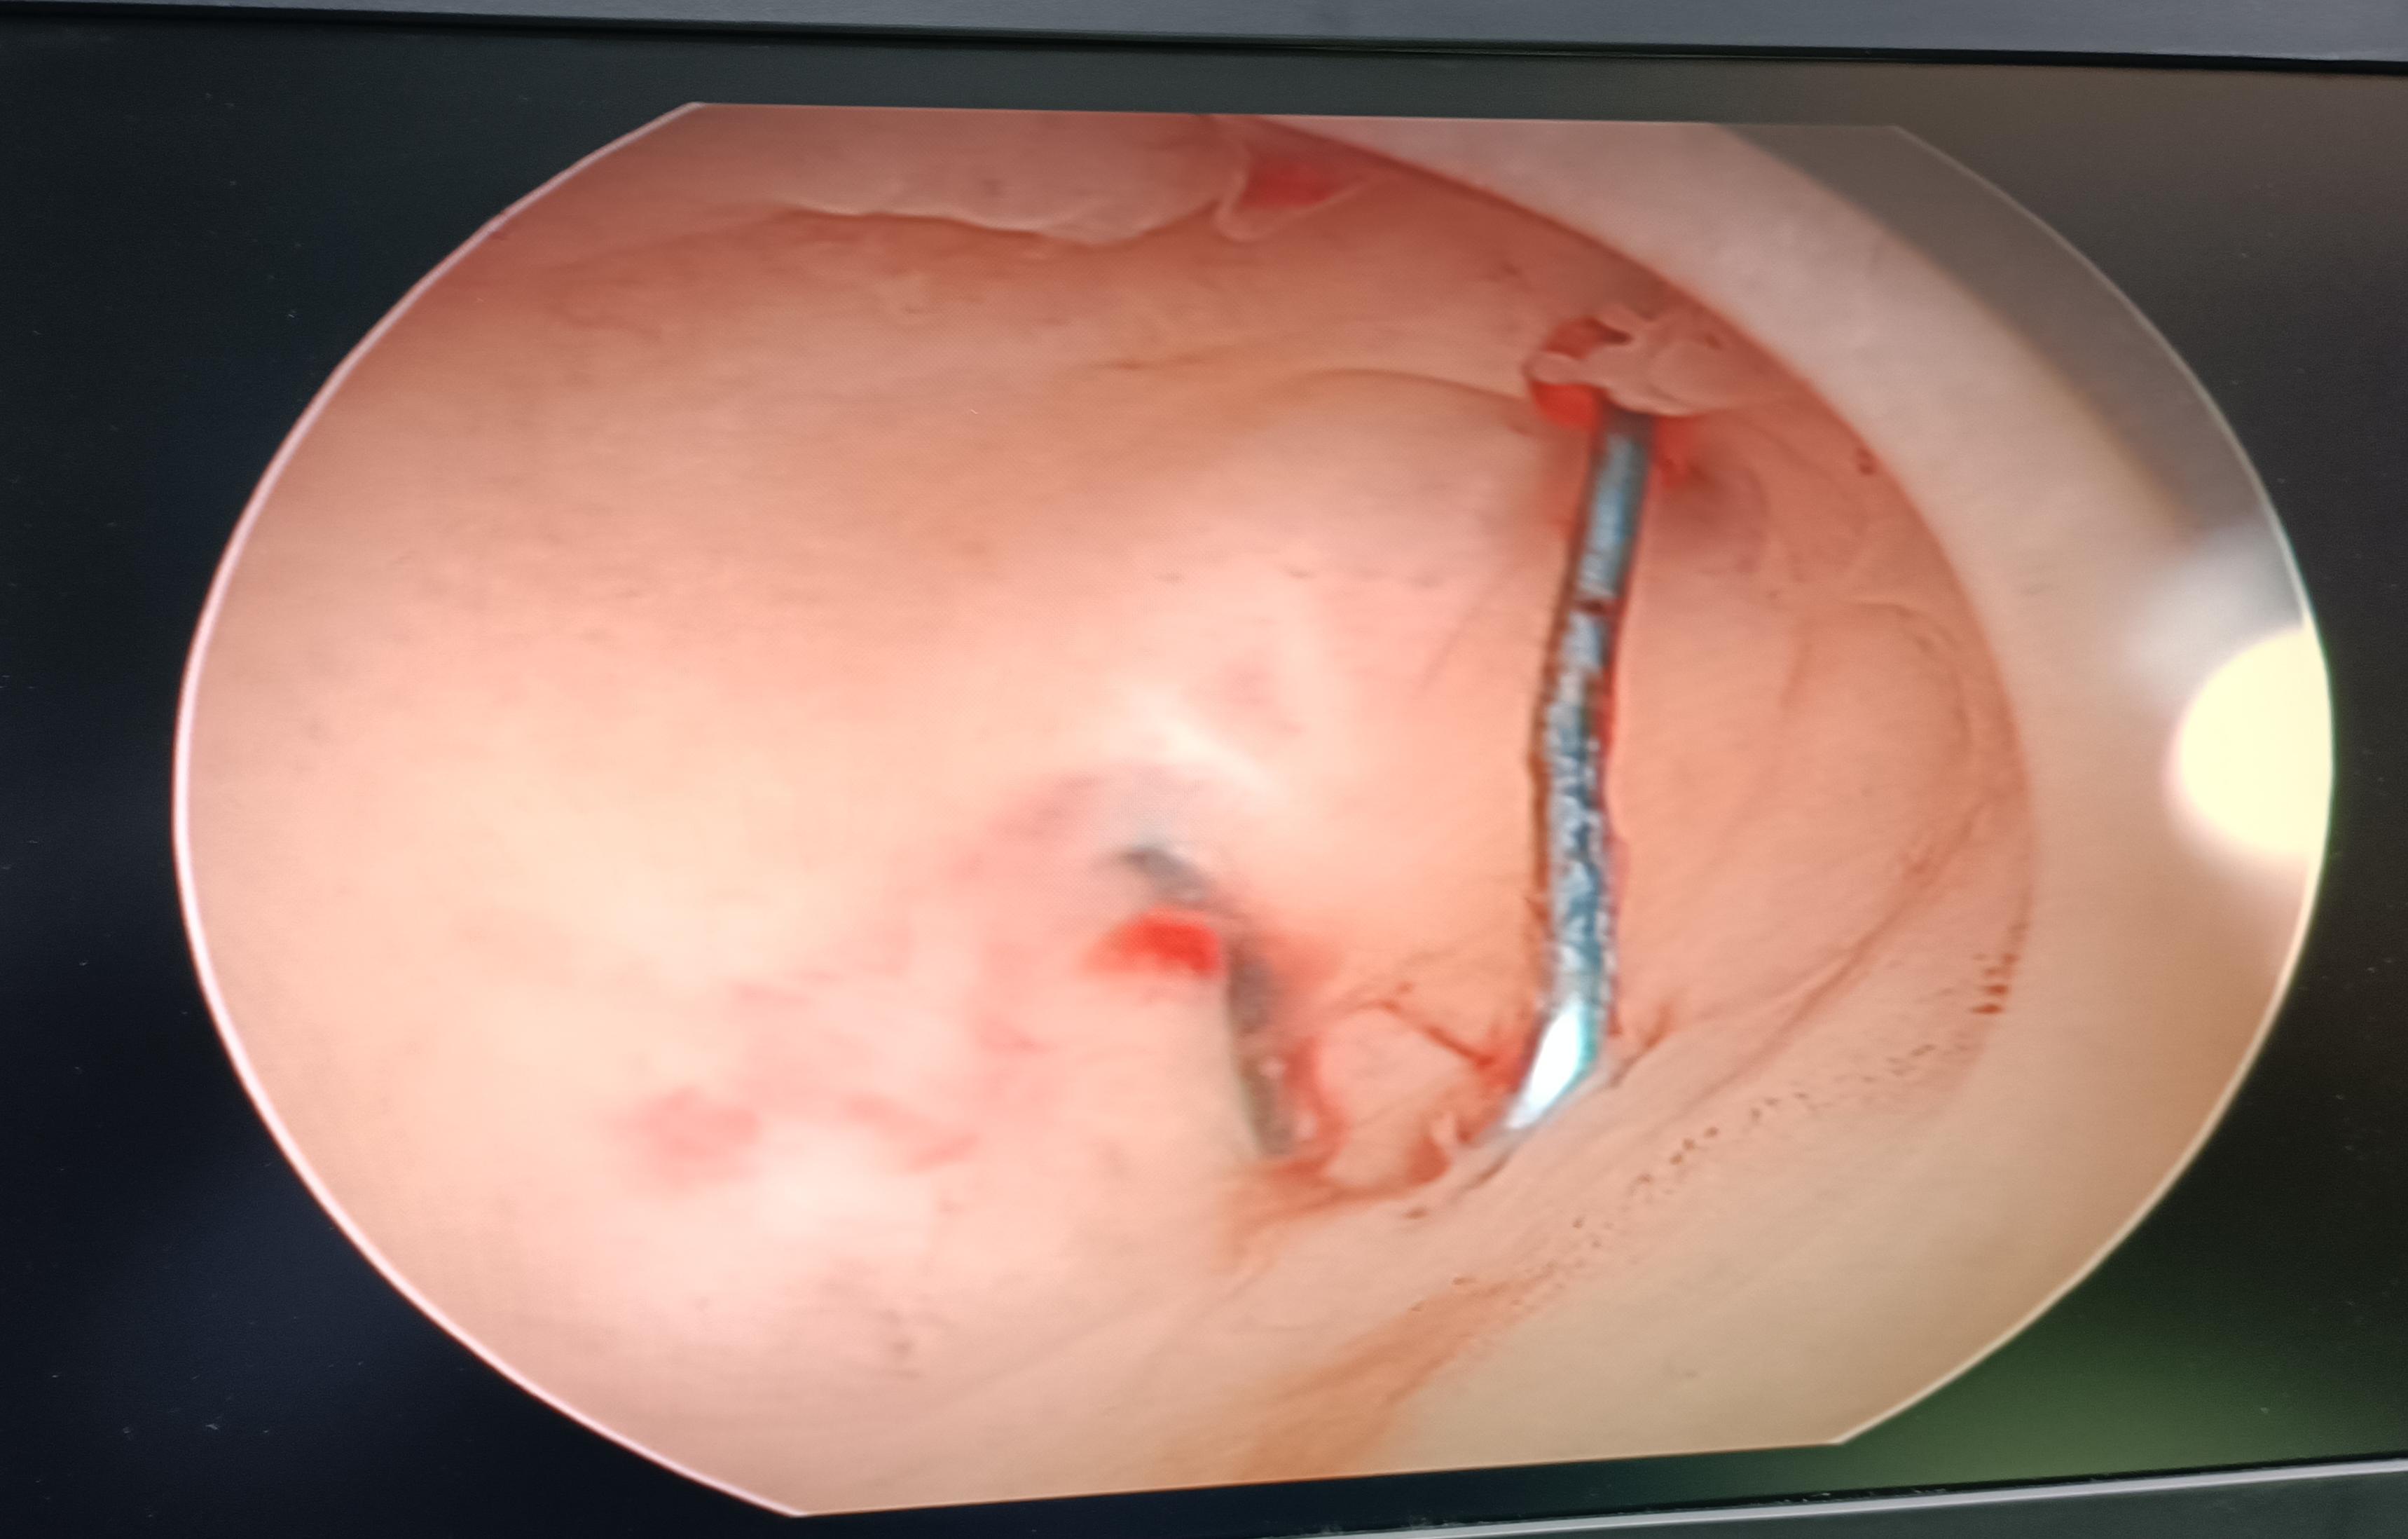

李利平主任携团队组织综合外科主任李志东,泌尿外科副主任医师郭亮、麻醉手术中心主任夏冰和护士长薛新广多次反复讨论,力求让患者肠道膀胱零损伤,最终确定手术损伤最小风险极大的手术方案:宫腹腔镜联合。术中先行宫腔镜检查,发现为“爱母环”,且其两侧铜臂已经嵌顿,后腹腔镜进腹,见子宫与大网膜、膀胱致密粘连,分离粘连过程中发现节育器两侧铜臂均已嵌入膀胱及大网膜里,联合普外科李志东主任及泌尿外科郭亮主任上台协助手术,使节育器完整取出,同时做到膀胱及肠管无损伤,期间手术室及麻醉科全力配合,圆满完成手术。术后一天便能下地行走自行进食。